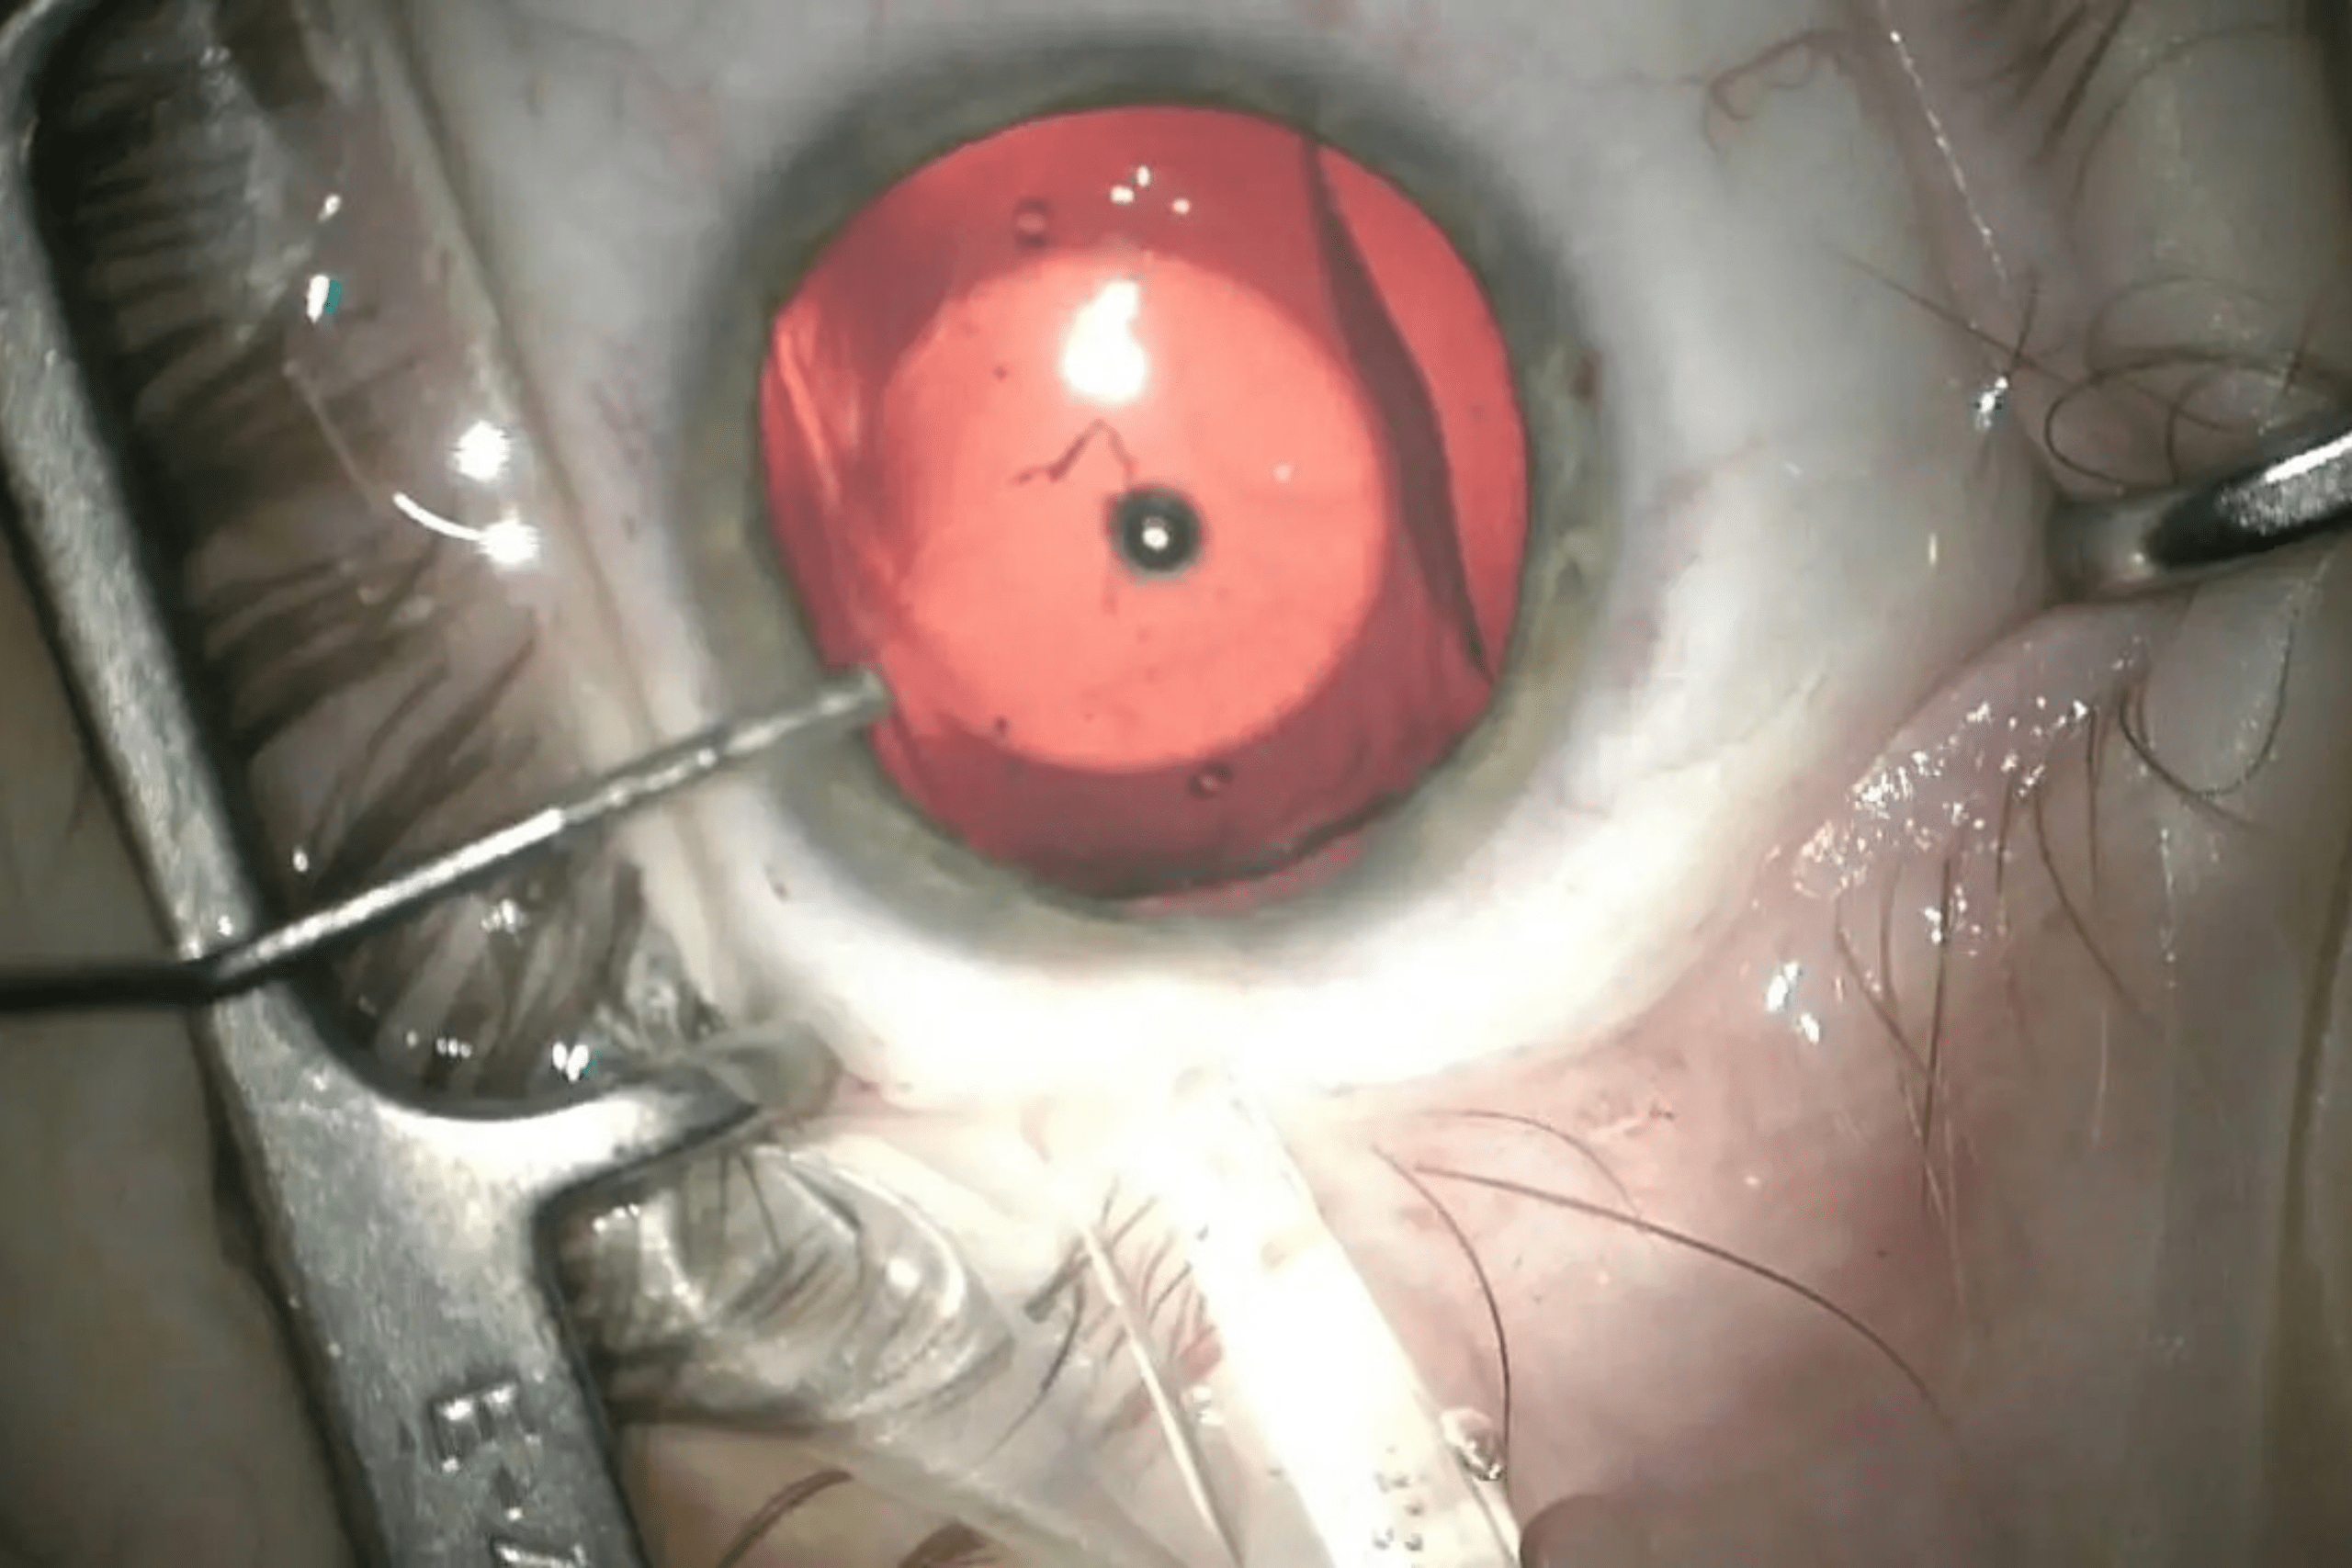

ICL surgery, or Implantable Collamer Lens surgery, is an advanced vision correction procedure designed for people with moderate to severe myopia (nearsightedness), hyperopia (farsightedness), or astigmatism. Instead of reshaping the cornea like LASIK, ICL involves implanting a soft, flexible, biocompatible lens between the iris and the natural lens of the eye. This lens helps to correct refractive errors and improve vision clarity without removing any natural eye tissue.

The procedure is quick, typically taking 20–30 minutes per eye, and recovery is usually fast with minimal discomfort. ICL is ideal for those with thin corneas, dry eyes, or unstable prescriptions. It’s reversible and offers long-term vision improvement with excellent visual outcomes.